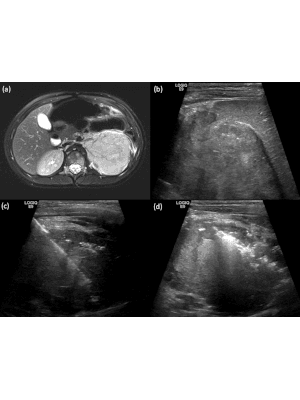

Historically, paediatric tumour biopsies were undertaken using an open surgical technique, but this is invasive and confers morbidity. Now, given the advances in paediatric interventional radiology (IR) techniques, there is a growing preference for tumour biopsies in children to be performed using a percutaneous image-guided technique as this has been shown to be accurate and safe. The majority of paediatric soft tissue tumour biopsies can be performed using ultrasound guidance but sometimes advanced modalities, such as contrast-enhanced ultrasound (CEUS), CT or cone beam CT (CBCT) and image fusion are required. This article describes some of these techniques with case examples.